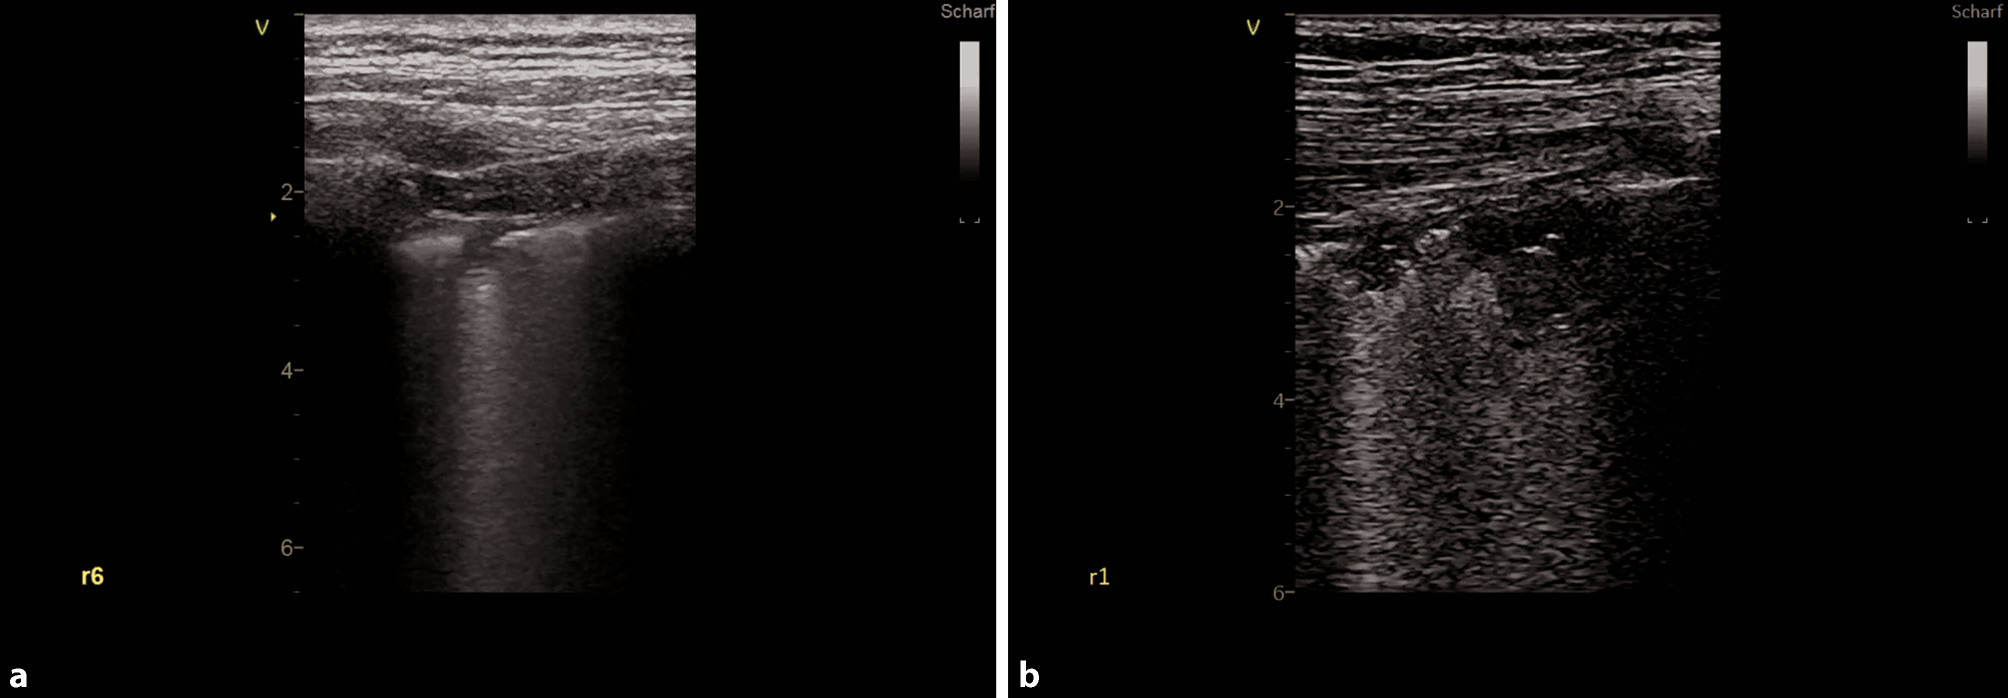

Fig. 6

Small consolidations in COVID-19. a Small consolidation with comet tail artifact in zone 6, right hemithorax. b Two small consolidations in zone 1, right hemithorax